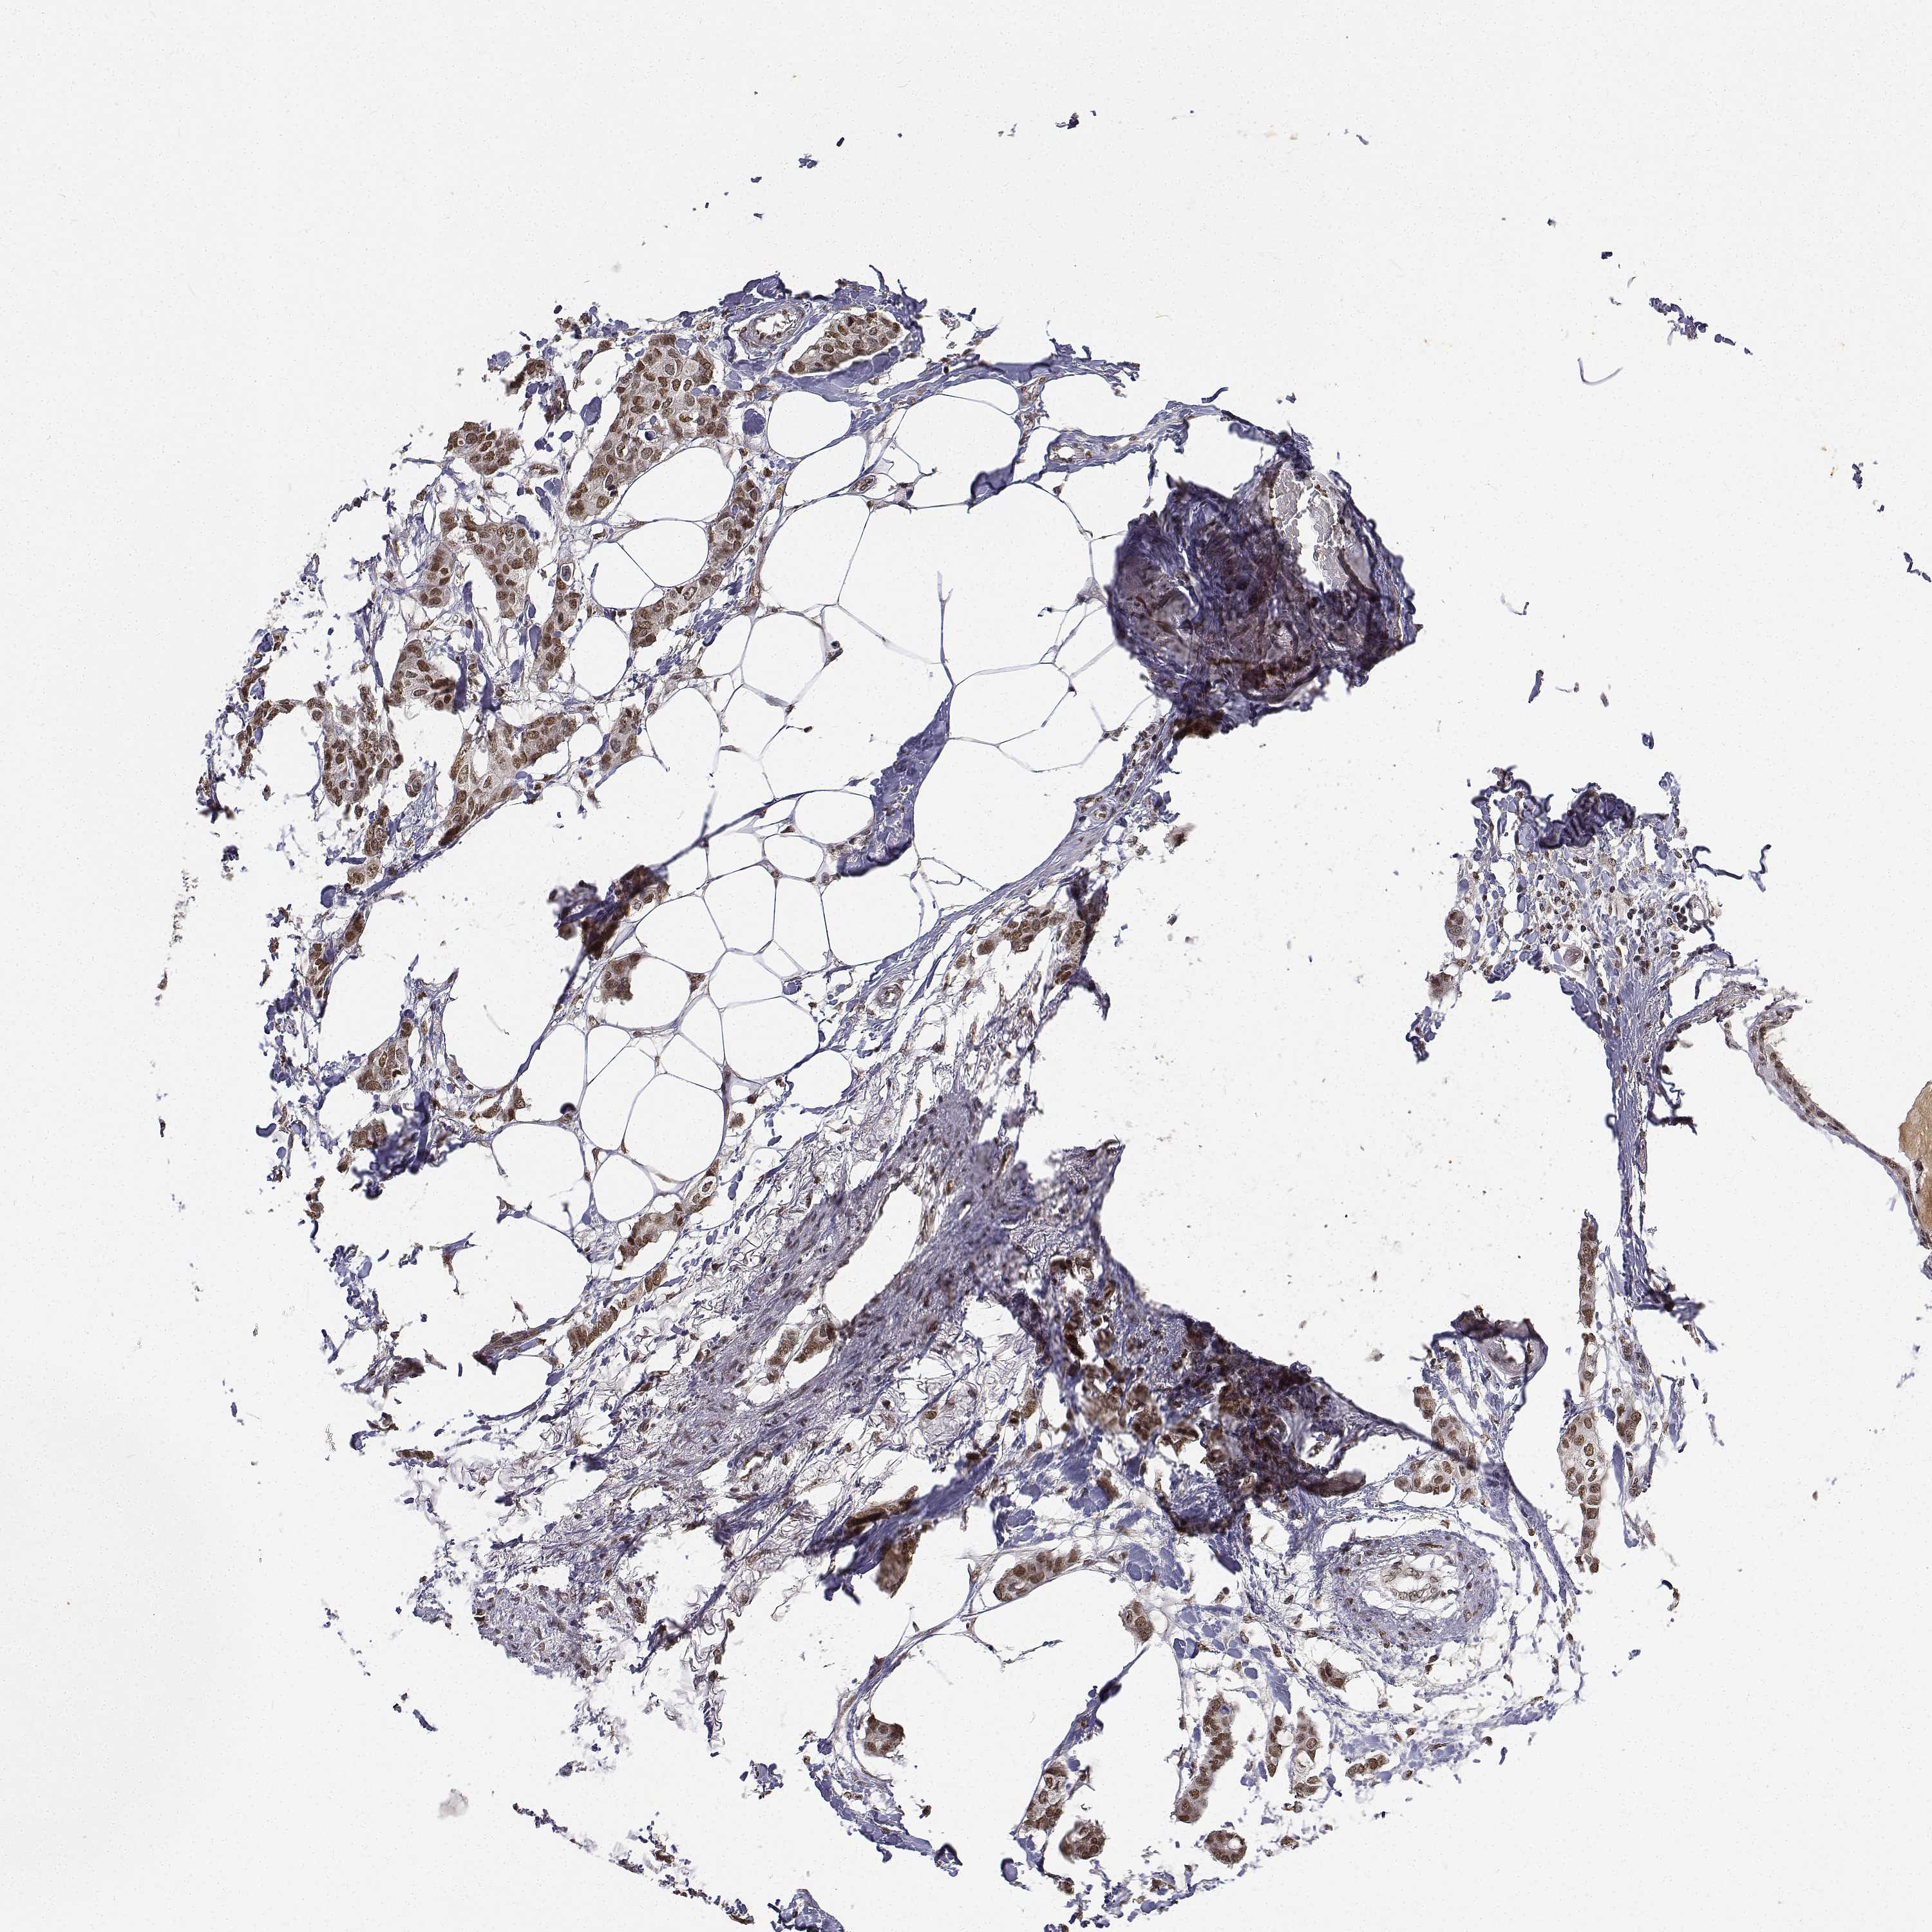

CANCER BREAST CANCER Show tissue menu

BRCA TCGA BRCA VALIDATION PROTEIN EXPRESSION